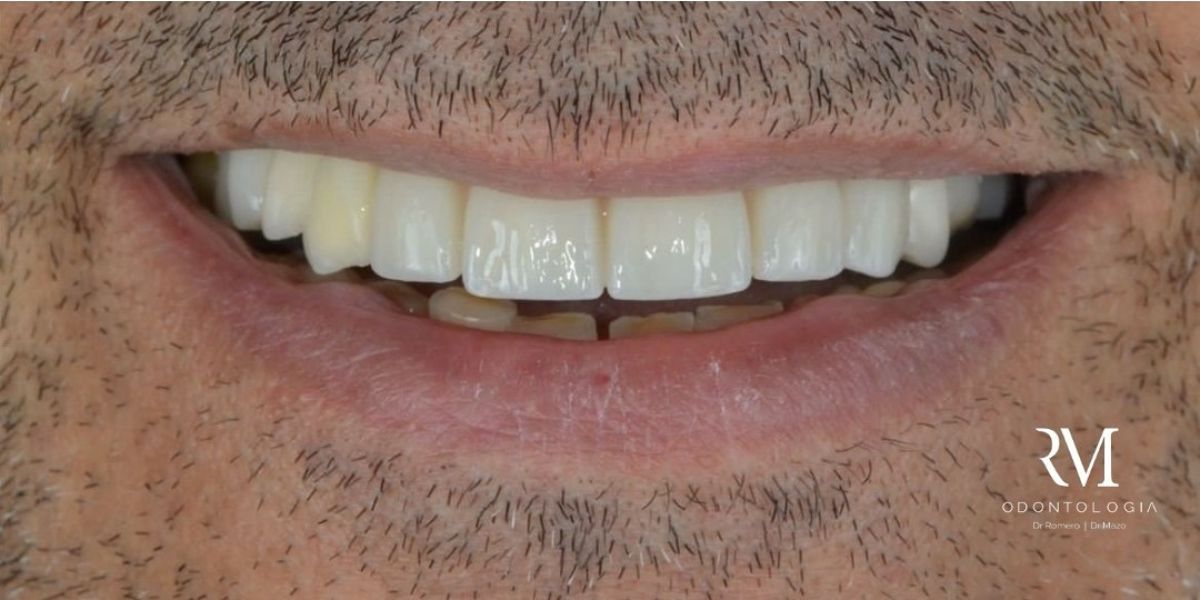

Bienvenido a RM Odontología. Aquí empieza tu sonrisa.

Devolver confianza, funcionalidad y sonrisas seguras a nuestros pacientes.